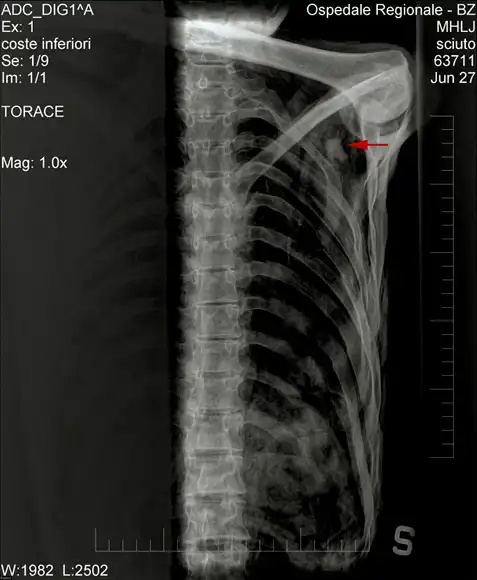

Рентген плеча «ледяного человека», наконечник стрелы отмечен красной стрелкой.

Доктор Эдвард Эгартер Вигль с коллегами с помощью эндоскопа изучают наконечник стрелы, засевшей в плече мумии. Стрела перебила артерию, вызвав большую потерю крови.